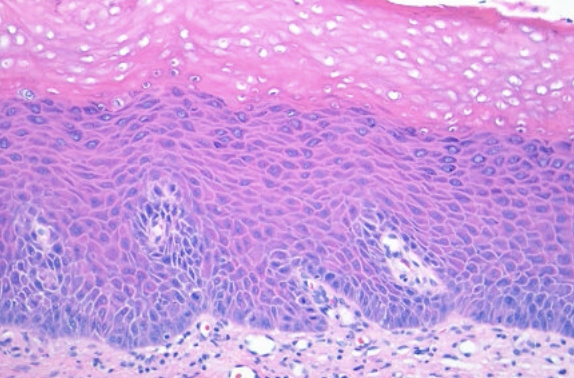

廣底、papillary 突起不明顯、Koilocytes (空亮、葡萄乾核)  |

組織

- Cell 分三類:

- A: Epithelioid (在 epi)

- B: Lymphocyte-like

- Spindle-shaped

- Compound (在 epi., dermis 之間) 或 Intradermal

- 只有 Junctional 會呈現 Tear-like Nest

- Indian-file pattern: 鑽進 Dermis 排成一排

- 深層可能圍皮膚附屬物、神經